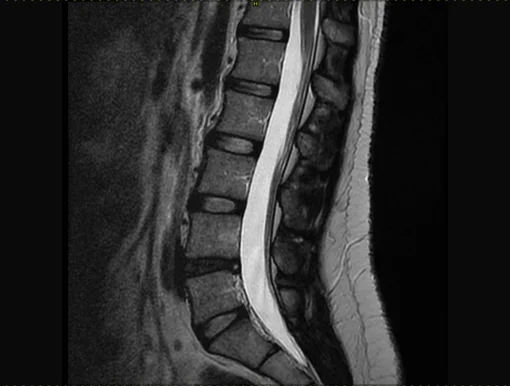

According to biological aging, degeneration runs in different phases. Initially, the water retention capacity decreases, resulting in a possible painful segmental hypermobility. During this phase, diagnostic imaging is often inconclusive. X-rays can show retrolisthesis, a reverse sliding of the upper vertebra over the lower vertebra. In the MRI, the affected intervertebral disc appears plain black (black disc), sometimes a small collection of fluid is seen in the rear fiber ring (annular tear), which is accepted as apparent pain symptom.

During the further course of the process, substance of the intervertebral disc is decreasing, disc height is diminished, leading, regardless of protrusions and/or herniations, to narrowing of the nerve exits, a lateral narrowing of the spinal canal called lateral stenosis. Advanced stages of degeneration lead to a complete loss of disc height causing complete narrowing of the spinal canal (central stenosis). X-rays and MRI show typical signs as well. Although increased stiffening can be assumed in the advanced stages, segmental instabilities can regularly be found, causing pain.